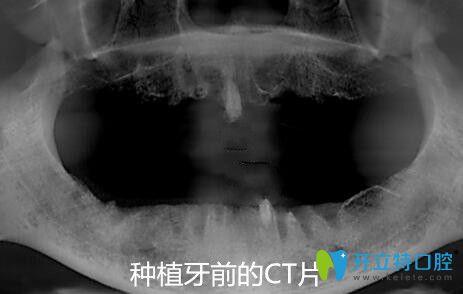

我在寧波恒美口腔做allon4種植前前的CT片

從面診到拍CT片、身體的多種常規(guī)檢查等,一樣不漏;統(tǒng)統(tǒng)做完后才制定修復方案。方醫(yī)生說從各種檢查情況來看,我比較適合做全口ALL-ON-4種植牙,這樣不僅省錢,手術速度快、創(chuàng)傷也很小。